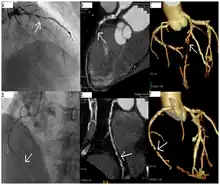

Coronary catheterization is one of the several cardiology diagnostic tests and procedures. Specifically, through the injection of a liquid radiocontrast agent and illumination with X-rays,[1] angiocardiography allows the recognition of occlusion, stenosis, restenosis, thrombosis or aneurysmal enlargement of the coronary artery lumens; heart chamber size; heart muscle contraction performance; and some aspects of heart valve function. Important internal heart and lung blood pressures, not measurable from outside the body, can be accurately measured during the test. The relevant problems that the test deals with most commonly occur as a result of advanced atherosclerosis – atheroma activity within the wall of the coronary arteries. Less frequently, valvular, heart muscle, or arrhythmia issues are the primary focus of the test.

During coronary catheterization (often referred to as a "cath" or "cardiac cath" by physicians), blood pressures are recorded and fluoroscopy (X-ray motion picture) shadow-grams of the blood inside the coronary arteries are recorded. In order to create the X-ray pictures, a physician guides a small tube-like device called a catheter, typically ~2.0 mm (6-French) in diameter, through the large arteries of the body until the tip is just within the opening of one of the coronary arteries. By design, the catheter is smaller than the lumen of the artery it is placed in; internal (intra-arterial) blood pressures are monitored through the catheter to verify that the catheter does not block blood flow (as indicated by "dampening" of the blood pressure).

The catheter is itself designed to be radiodense for visibility and it allows a clear, watery, blood compatible radiocontrast agent, commonly called an X-ray dye, to be selectively injected and mixed with the blood flowing within the artery. Typically 3–8 cc of the radiocontrast agent is injected for each image to make the blood flow visible for about 3–5 seconds as the radiocontrast agent is rapidly washed away into the coronary capillaries and then coronary veins. Without the X-ray dye injection, the blood and surrounding heart tissues appear, on X-ray, as only a mildly-shape-changing, otherwise uniform water density mass; no details of the blood and internal organ structure are discernible. The radiocontrast within the blood allows visualization of the blood flow within the arteries or heart chambers, depending on where it is injected.

If atheroma, or clots, are protruding into the lumen, producing narrowing, the narrowing may be seen instead as increased haziness within the X-ray shadow images of the blood/dye column within that portion of the artery; this is as compared to adjacent, presumed healthier, less stenotic areas.

CT angiography can act as a less invasive alternative to Catheter angiography. Instead of a catheter being inserted into a vein or artery, CT angiography involves only the injection of a CT-visible dye into the arm or hand via an IV line. CT angiography lowers the risk of arterial perforation and catheter site infection. It provides 3D images that can be studied on computer, and also allows measurement of heart ventricle size. Infarct area and arterial calcium can also be observed (however those require a somewhat higher radiation exposure). That said, one advantage retained by Catheter angiography is the ability of the physician to perform procedure such as balloon angioplasty or insertion of a stent to improve blood flow to the artery.[8]